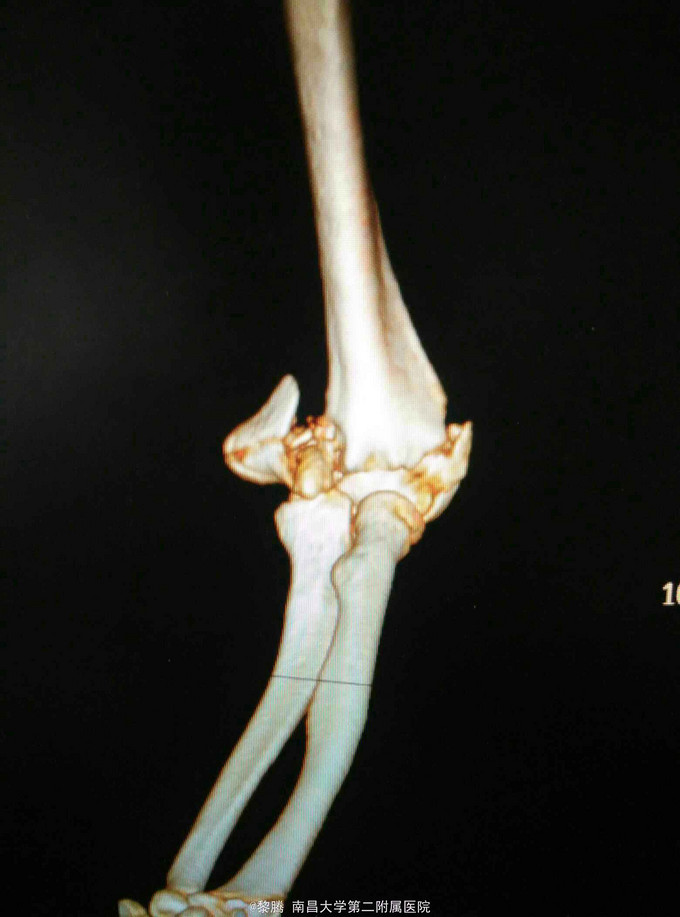

外伤致左肘关节肿痛,活动受限6小时 患者中年女性,因外伤致左肘关节肿胀、疼痛明显,伤后左肘关节当即无法活动,于当地医院摄片提示左肱骨髁间骨折,既往病史无特殊。

查体:左肘关节肿胀明显,局部压痛明显,可及骨擦感,关节活动受限,桡动脉搏动存在,肢体末梢感觉无异常。 辅查:左肘关节CT提示左肱骨髁间粉碎性骨折。

诊断:左肱骨髁间粉碎性骨折 治疗:骨折切开复位内固定+尺神经前置术